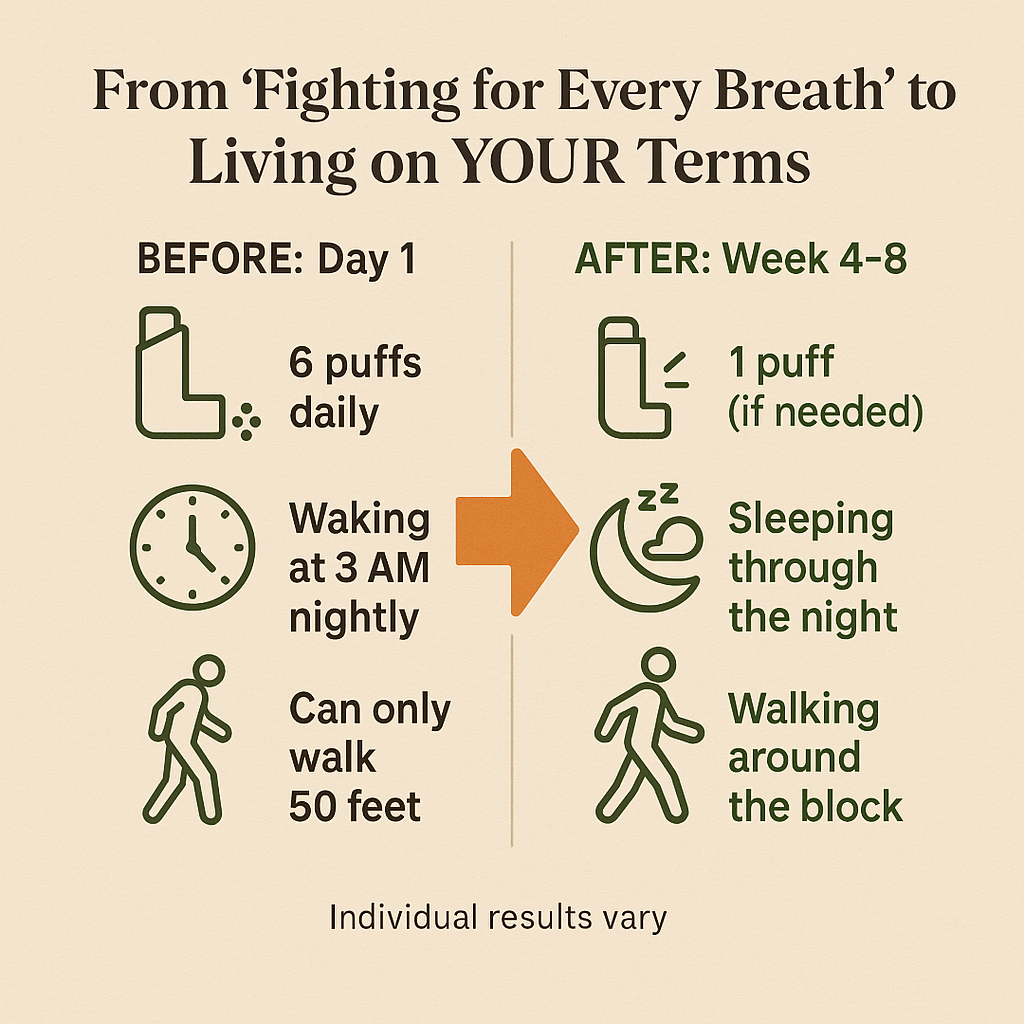

“For years I relied on inhalers and still felt like I was suffocating. I never thought I’d be able to leave the house without worrying about my breathing. Since using these drops, I can walk, climb stairs, even go outside without panic. It’s given me my freedom back.”

✅ Wakeup without gasping

✅ Enjoy time with your family again

✅ Go through your day without fear